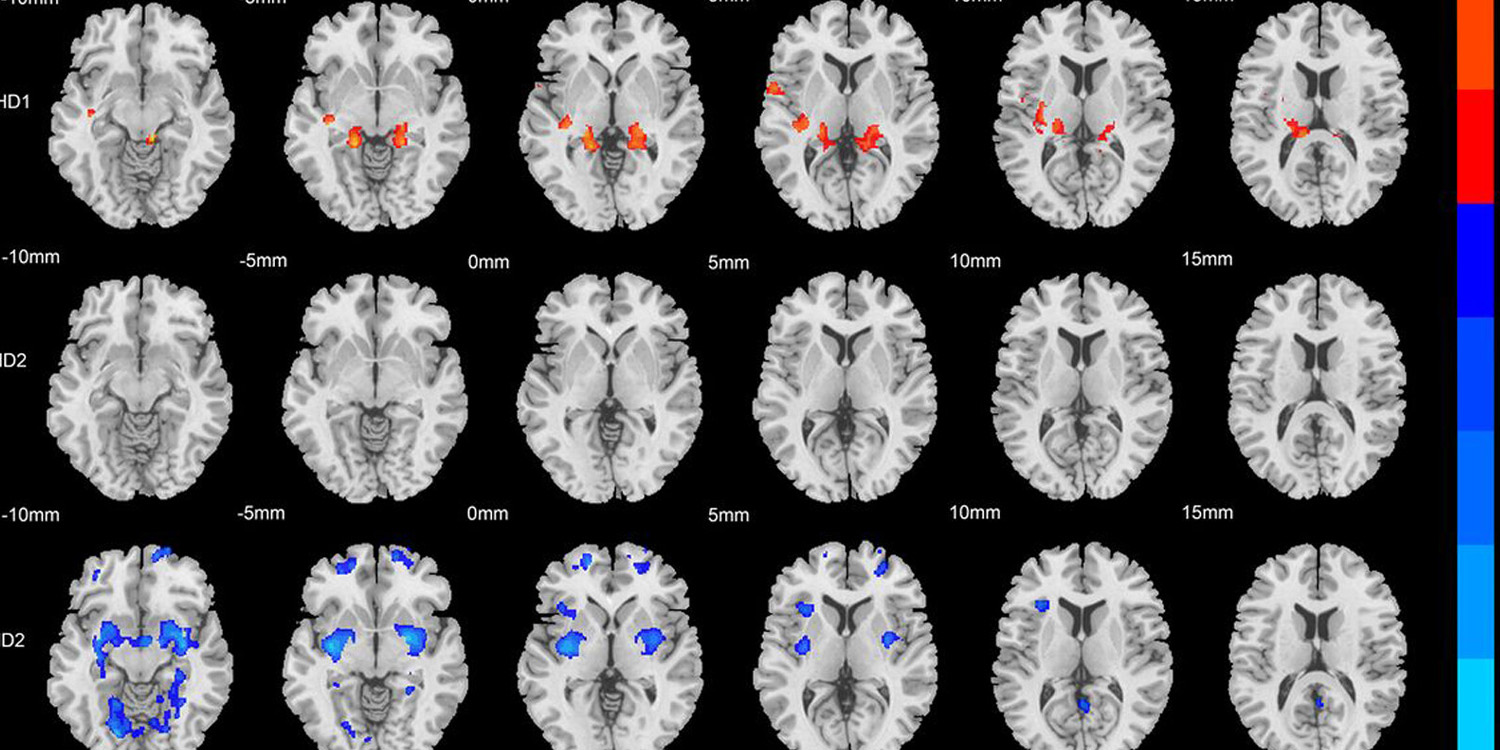

Brain scans reveal two distinct physical subtypes of ADHD - PsyPost

A new study reveals that attention-deficit/hyperactivity disorder actually consists of at least t...